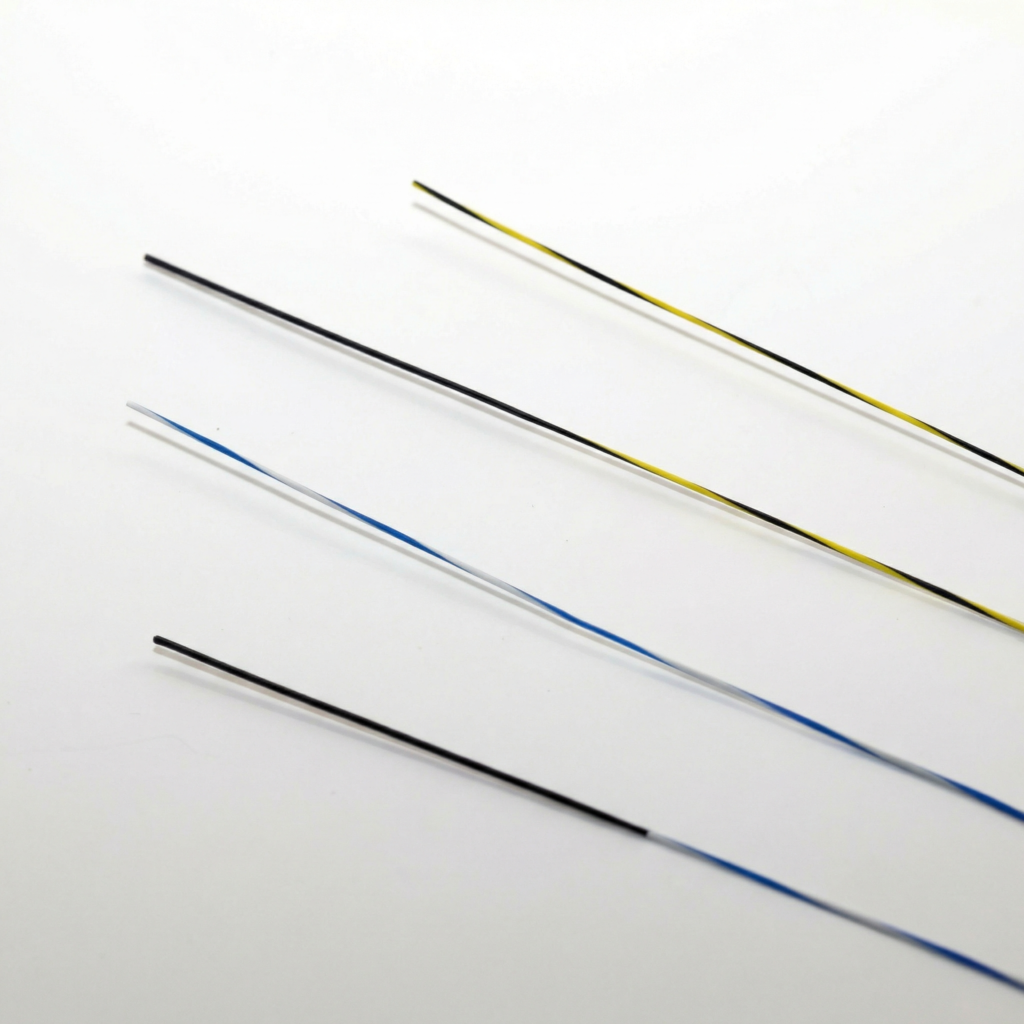

ARIA Wire Rapid Guid – Fio Guia Hidrofílico

Fio Guia Hidrofílico

O fio guia hidrofílico possui revestimento especial que reduz o atrito, proporcionando passagem suave mesmo em trajetos tortuosos ou estreitos. Ideal para acessos difíceis e manipulação atraumática.